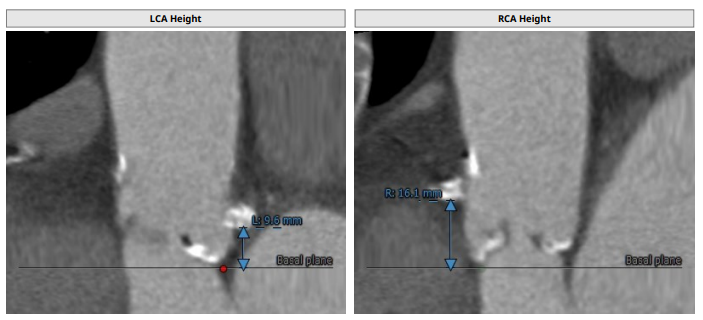

主动脉根部解剖CT影像

左冠高度:9.6 mm,右冠高度:16.1 mm。

钙化积分:61.2mm³,轻度钙化。